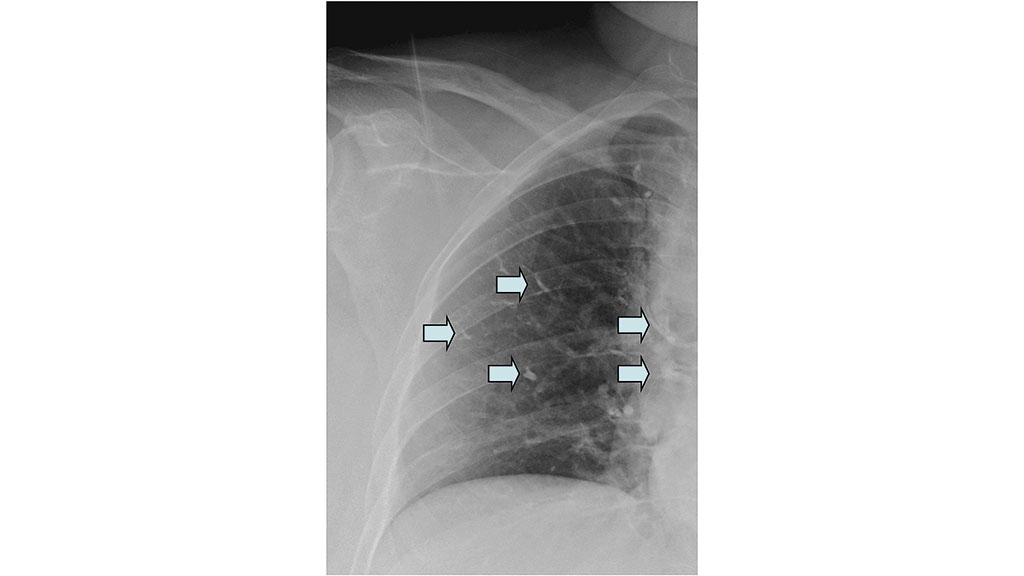

Obwohl die Komplikationsmöglichkeiten im Rahmen des Eingriffes neben den allgemeinen Operationsrisiken der Wirbelsäulenchirurgie (Blutung, Verletzung der Dura und gegebenenfalls des Myelons etc.) teilweise vital bedrohliche Ereignisse wie z. B. ausgeprägte Zementembolien (Abb. 4 bis 6) umfassen, fehlt den Verantwortlichen teilweise die erforderliche Kompetenz, diese Komplikationen zu beherrschen 23 24 25. Trotz der geringen Operationsdauer von durchschnittlich 20 bis 30 Minuten pro Wirbelkörper bedeutet alleine schon die für die Operation erforderliche Bauchlagerung für alte und multimorbide Patienten eine zusätzliche Belastung – in seltenen Fällen kommt es intraoperativ zu Kreislaufstillständen mit Todesfolge, auch wenn Reanimationsmaßnahmen sofort greifen und eine Weiterbehandlung auf einer Intensivstation (kleinere Krankenhäuser verfügen teilweise über keine ITS) gewährleistet ist.